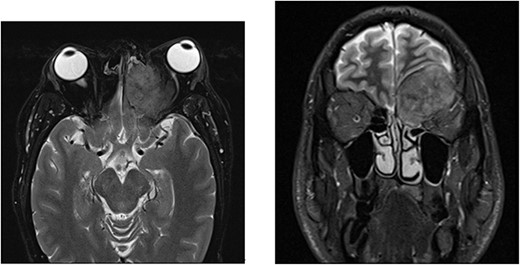

A 52-year-old male initially presented with preseptal cellulitis, which was successfully treated with antibiotics. One month later, he developed protrusion of the left eye with numbness over the left eyelid and ipsilateral forehead. No diplopia or signs of optic nerve compression were observed. A computed tomography (CT) scan revealed a large mass sized 36 × 31 x 29 mm centred over the left orbital roof, damaging bone and extending superiorly into the anterior cranial fossa, inferiorly into the orbit, as well as medially into the left olfactory and left nasal fossa (Fig. 1). It was reported as a sclerotic lesion with soft tissue elements. Another 25-mm lesion in the skull base infiltrated the right side of the clivus. These findings were confirmed by magnetic resonance imaging (MRI) of the head. The findings were then discussed at the Head & Neck multidisciplinary team meeting (MDT), where, considering the possibility that these might be metastatic deposits, an MRI was recommended to further characterize the lesion. It revealed extradural involvement of the left anterior cranial fossa without any evidence of intracerebral or leptomeningeal disease. Additionally, a thorax, abdomen, and pelvis CT with contrast showed multiple aggressive sclerotic lesions in the thoracolumbar spine and multiple nodules in the upper lobe of both lungs. No invasive mass in the prostate or abdomen, or inguinal lymphadenopathy was observed. Based on these findings, the MDT meeting recommended a transnasal tissue biopsy, which revealed an adenocarcinoma (Fig. 2). Immunohistochemical results were keratin positive, largely negative for CK 7 and 20, as well as negative for other markers, suggesting a prostatic origin. Prostate-specific antigen (PSA) marker test of the tumour cells was positive, indicating the prostate as the primary site.

MRI with contrast shows a large left anterior cranial fossa and extra-axial extradural solid mass involving the left olfactory groove with bony erosion. There is a large component on the superior and medial extraconal orbital causing left proptosis. Direct involvement of the left frontal sinus is observed. (a) Axial view. (b) Coronal view.